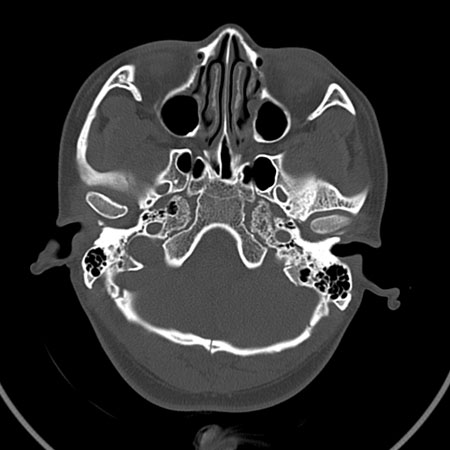

请问各位战友:图示箭头处是否为颅骨骨折?

病史:患者,女,20岁.头部及腹部外伤20分钟.伤后昏迷,无呕吐.头及右侧腰背部疼痛,双侧瞳孔等大,

右肾区叩痛.其它无异常.患者家属否认原有外伤史.

请大家看看是否为颅骨骨折.还是正常变异,或为陈旧骨折.谢谢.

图片未上传完,所见图象示枕骨线样低密度影,边缘锐利,结合外伤史,伤后昏迷,骨折不能除外。

枕骨的线样低密度影锐利、清晰,但正好位于矢状缝的位置,局部无明显软组织肿块,相临及对冲部位脑实质亦无出血及挫裂伤表现。

单就这几层暂不考虑骨折,建议上传完整图片。

楼主所关心的另一个线样影应该是头颅矢状面略偏左,射线正好穿过所致,不需要考虑骨折。

枕骨是单块的,矢状缝是在顶骨而不是在枕骨,枕骨后缘见线状低密度,边缘税利,考虑在骨折存在。

枕后部及左侧颞枕部边缘锐利的线样低密度影,局部软组织无异常,左侧乳突蜂房密度均匀,硬膜下及脑实质内未见出血灶,考虑为正常变异。

枕部考虑骨折。一般的颅逢不会跨越板障,楼主所示枕骨断面两侧板障也不连续。